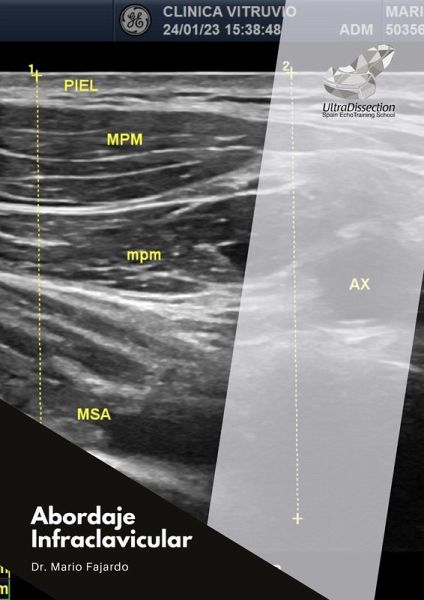

Desde las primeras páginas, el lector es llevado de la mano a través de fundamentos anatómicos, indicaciones precisas y mitos comunes sobre el procedimiento, como el temido riesgo de neumotórax. Con apoyo de ilustraciones clínicas y ecográficas (como se muestra en la imagen de la página 7, que compara la distancia piel-pleura), Fajardo construye un argumento sólido que invita al lector a perderle el miedo a esta técnica.